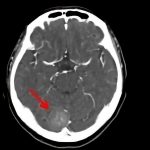

断層撮影